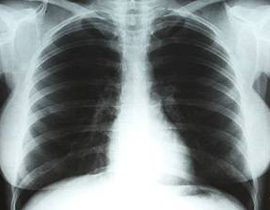

أي مبلغ كنت مستعد أن تدفع مقابل صدر النجمة الأمريكية الراحلة مارلين مونرو؟ هذا السؤال مطروح اليوم في المزاد العلني. منذ 56 سنة، دخلت ملكة الإغراء الأمريكية الراحلة، مارلين مونرو، إلى ما كان اسمه في ذلك الوقت "مستشفى أرز لبنان" الذي اعتادت التردد عليه في لوس أنجلس كلما ألمت بها محن صحية، وهناك أجروا لها عملية جراحية بسيطة في الرحم سبقها كشف عام أجراه عليها طبيب اعتمد فيما اعتمد بفحوصاته على صورة بالأشعة التقطت هناك لصدرها الذي كان أحد أسباب تربعها على عرش الإغراء العالمي منذ بدأ نجمها الفني يلمع وهي ما زالت في سن المراهقة.

وتبدو مونرو عبر الصورة وقد وضعت يديها على خصريها وهي في حالة وقوف وملتصقة الصدر بلوح معدني تسربت منه أشعة إكس من جهاز عكس في الصورة التفاصيل الصحية لصدرها وبعض بطنها، مع أن العملية كانت لازالة ما كان يسبب لها آلاما في الرحم، وفق المنشور عن الصورة في كاتالوغ توصيفها للراغبين بشرائها عبر المزاد.